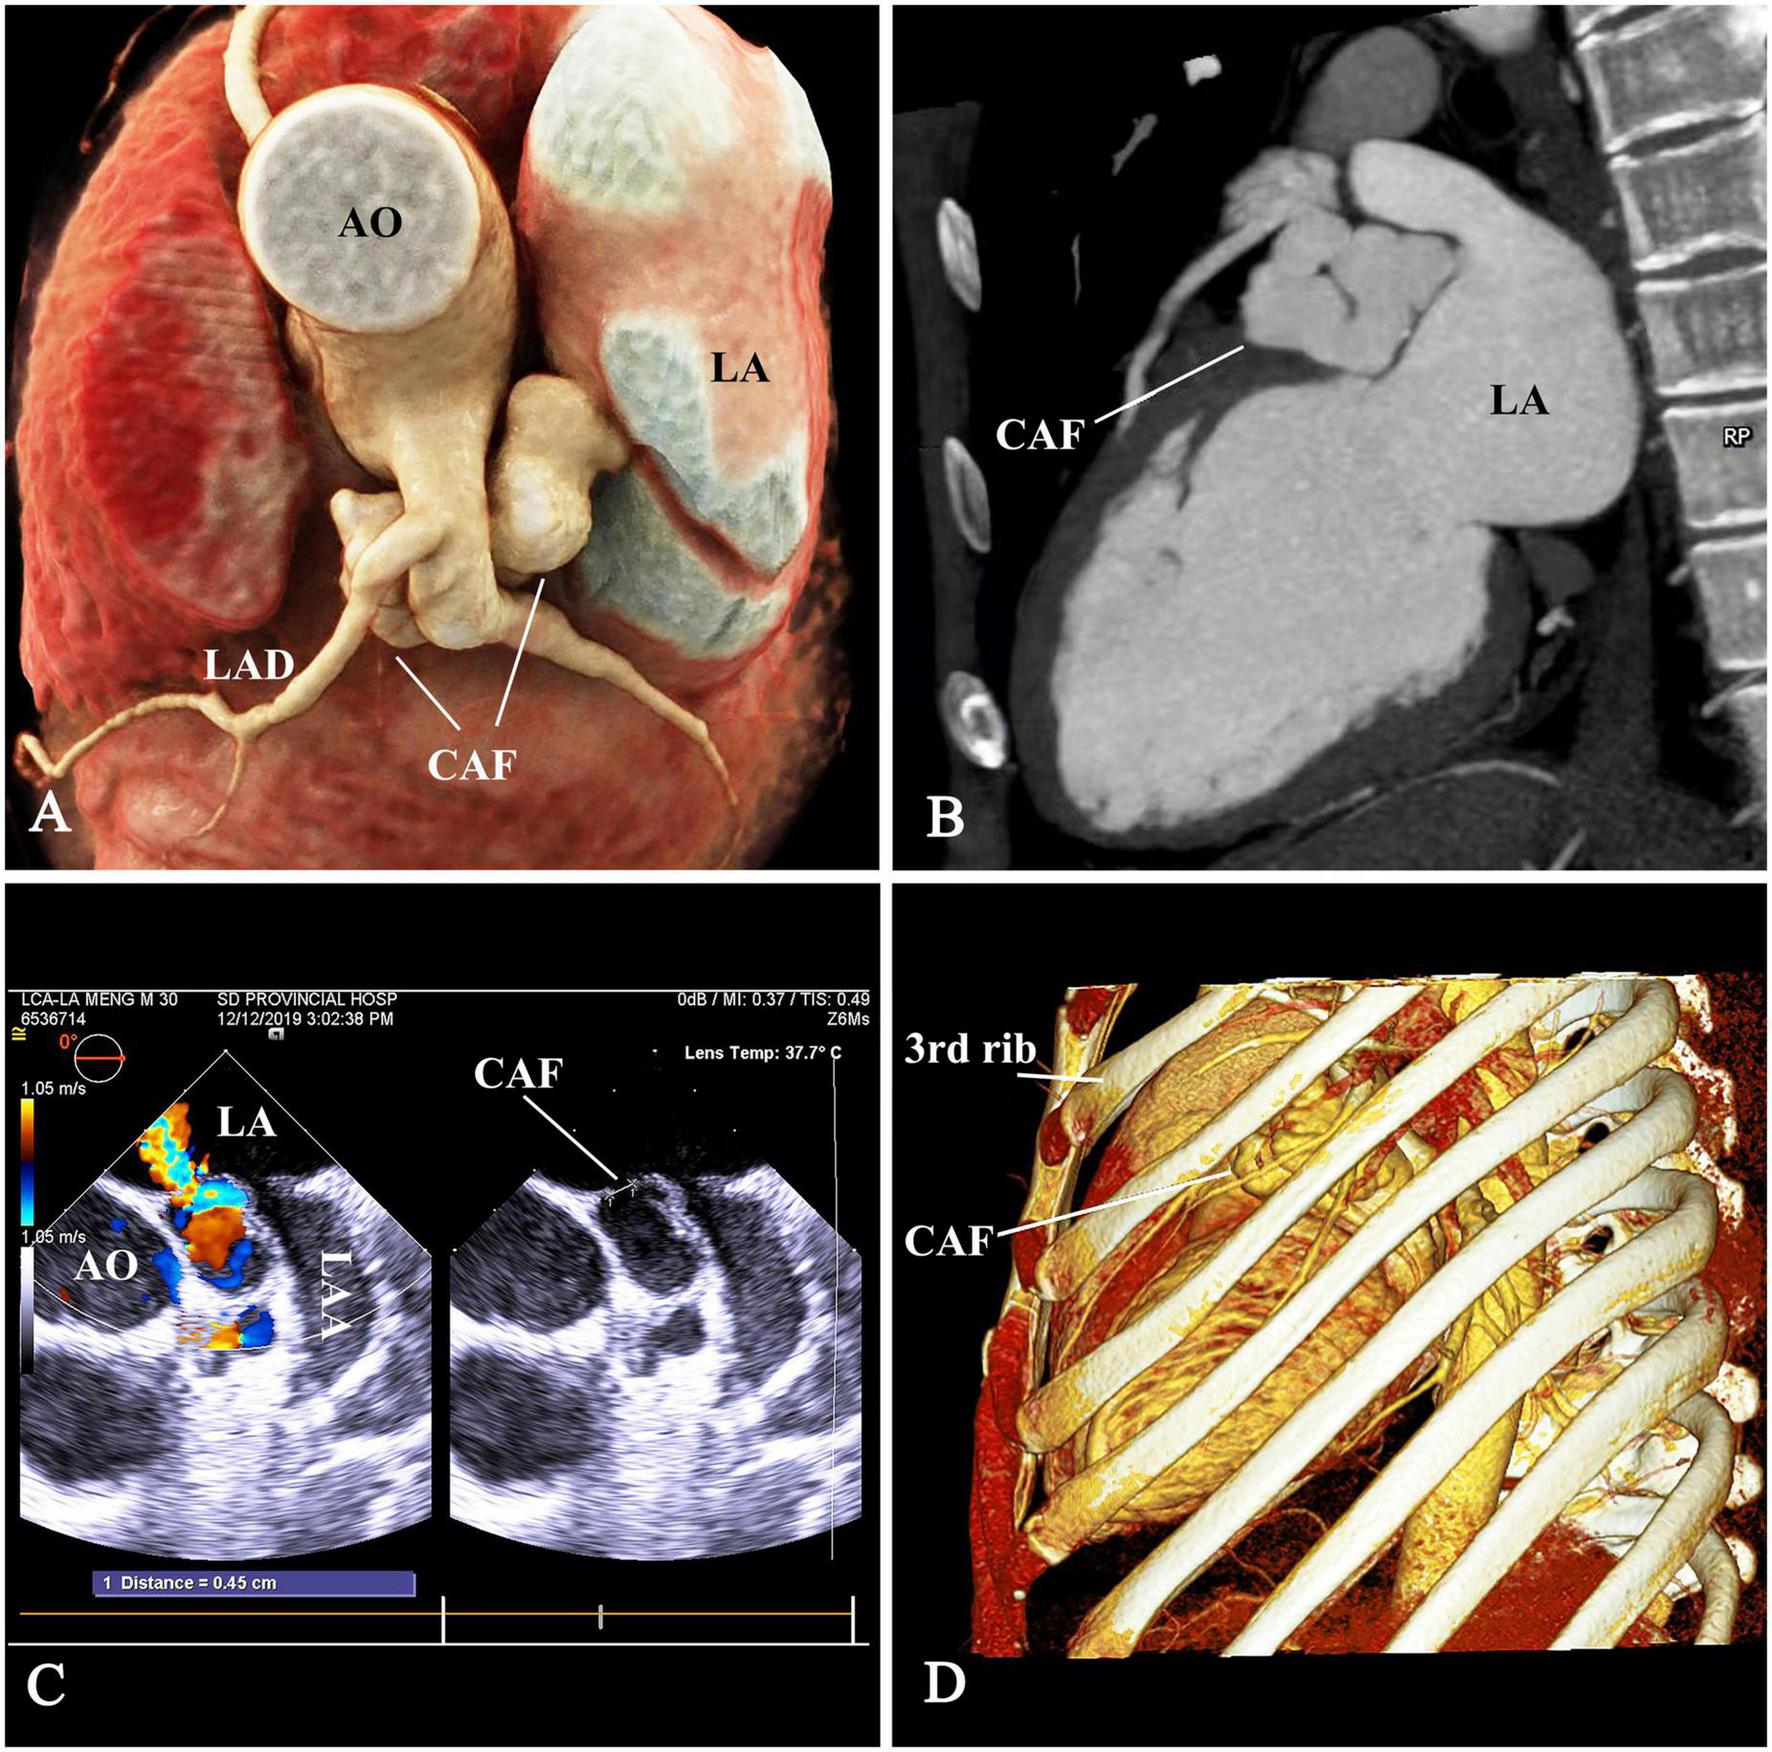

A 32-year-old man was admitted with a left scapular pain and diagnosed with a CAF by TEE and computed tomographic angiography (CTA). The TEE showed the CAF originated from main coronary artery (MCA) and drained into the LA with a continuous left-to-left shunt. The maximum inner diameter of the CAF was 11 mm and the left ventricular end diastolic diameter was 59 mm. The CTA was performed to delineate the anatomy of the CAF (Figures 1A–C). A continuous murmur was detected in the parasternal left 2nd and 3rd intercostal space. Non-specific electrocardiogram abnormalities were found. A bone-reserved thoracic CTA was also performed before the procedure to determine the exact location of the incision and procedure planning (Figure 1D). The informed consent was obtained.

FIGURE 1

The anatomy of CAF. (A,B) The tortuous aneurysmal CAF originated from main coronary artery (MCA), made a 180° turn underneath the LAD and MCA, and coursed backward to drain into the LA. (C) The drainage opening measuring 4.5 mm, was located at the LA roof between the aortic root and LAA. (D) The thoracic computed-tomographic-angiography to determine the access. CAF, coronary artery fistula; AO, ascending aorta; LAD, left anterior descending branch; LA, left atrium; LAA, left atrial appendage.